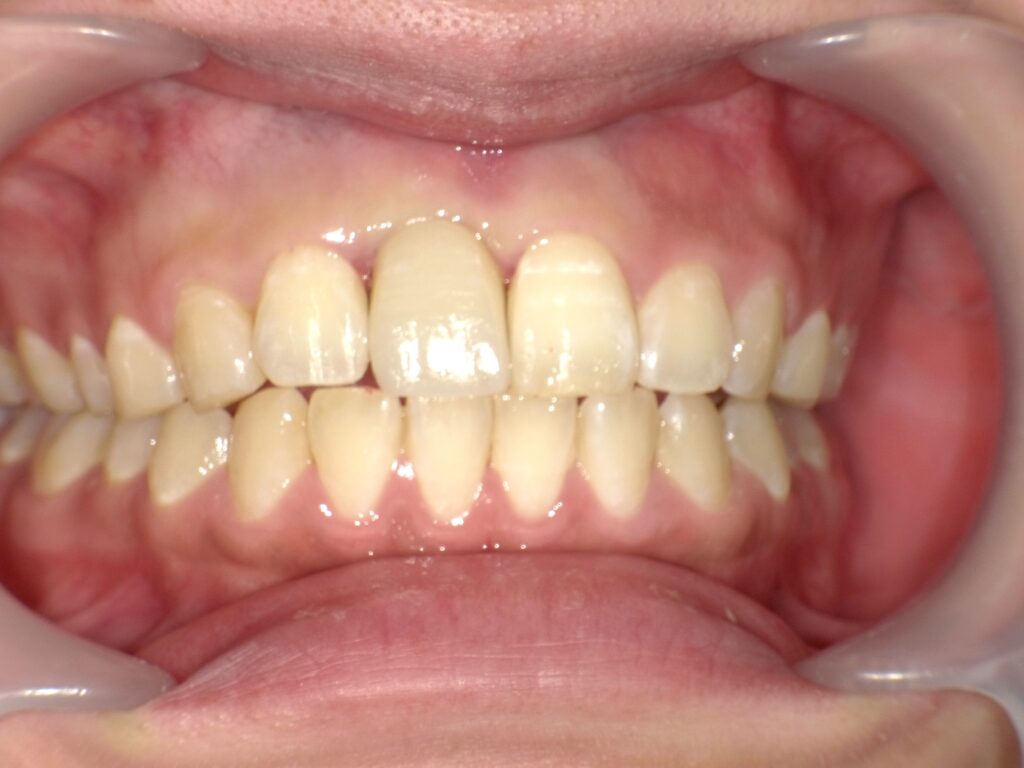

症例一覧 インプラント症例2 2024.11.25 治療内容インプラント主訴前歯事故で折れたのでインプラント治療を行いたい費用¥946,000(1本)治療期間7ヶ月 インプラント症例3 前の記事 インプラント症例1 次の記事